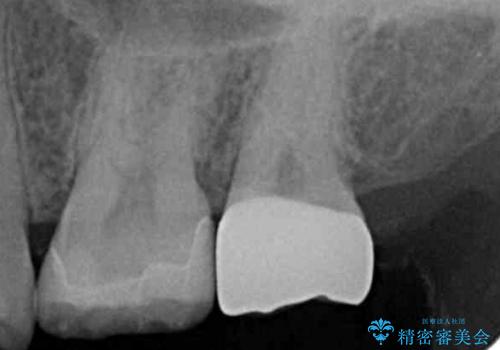

- 奥歯に穴が開いた気がするとのことで来院。

検査の結果、左上の奥歯に大きな虫歯があることが確認できました。

患者様のご希望もあり、今回はセラミックでの治療となりました。

- 左上6:セラミックインレー/77,000円 左上7:仮歯+ジルコニアクラウン/11,000+110,000円費用は治療当時の料金となります

歯の表面に穴が開くほどの虫歯は歯の中でかなり大きくなっていることが多いです。

虫歯の除去後は適合の良い修復物を入れることで今後の虫歯リスクを減らします。